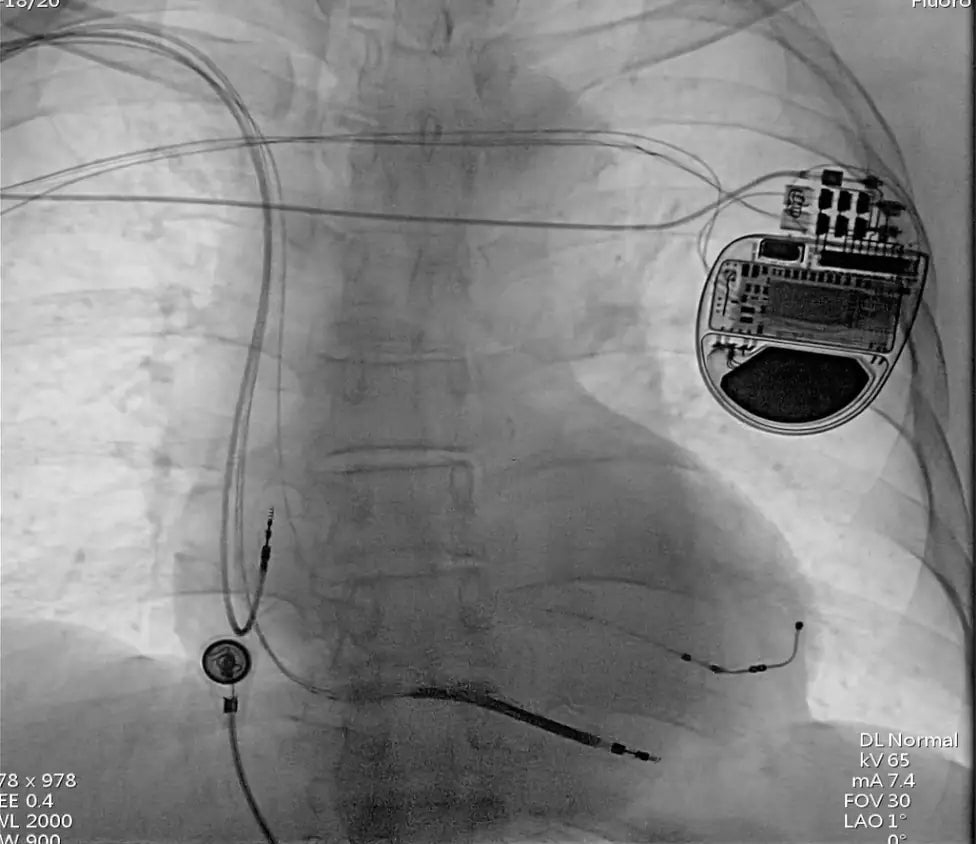

A multidisciplinary team led by Dr. Zhao Yonghui at Fuwai Hospital's Arrhythmia Unit recently performed a groundbreaking 15-hour surgery, successfully implanting a Cardiac Resynchronization Therapy Defibrillator (CRT-D) for a complex heart failure patient. The patient, a 56-year-old man from Dengfeng City, had suffered from multiple severe heart conditions, including dilated cardiomyopathy, Class IV heart failure, complete left bundle branch block, and extremely high-risk hypertension.

The procedure initially faced significant challenges when the team encountered a completely obstructed left axillary vein, which is the ideal access point for CRT-D implantation. In response, Dr. Zhao’s team quickly switched to a right-side access approach, creating a new subcutaneous tunnel for the device implantation.

Additionally, the patient’s target blood vessel was abnormally large, presenting difficulties in electrode stabilization. To address this, the team utilized a new type of spiral fixation electrode, which allowed for secure placement while avoiding nerve stimulation. The operation progressed successfully with meticulous adjustments, including connecting the right-side electrodes to the left heart defibrillator and completing the implantation.

This case is a rare and complex combination of challenges, including narrowing of the left subclavian and axillary veins, irregular target blood vessel anatomy, and the use of a subcutaneous tunnel. The success of this surgery highlights the advancement of cardiac medical technology and provides valuable clinical insights for treating severe heart failure in high-risk patients.